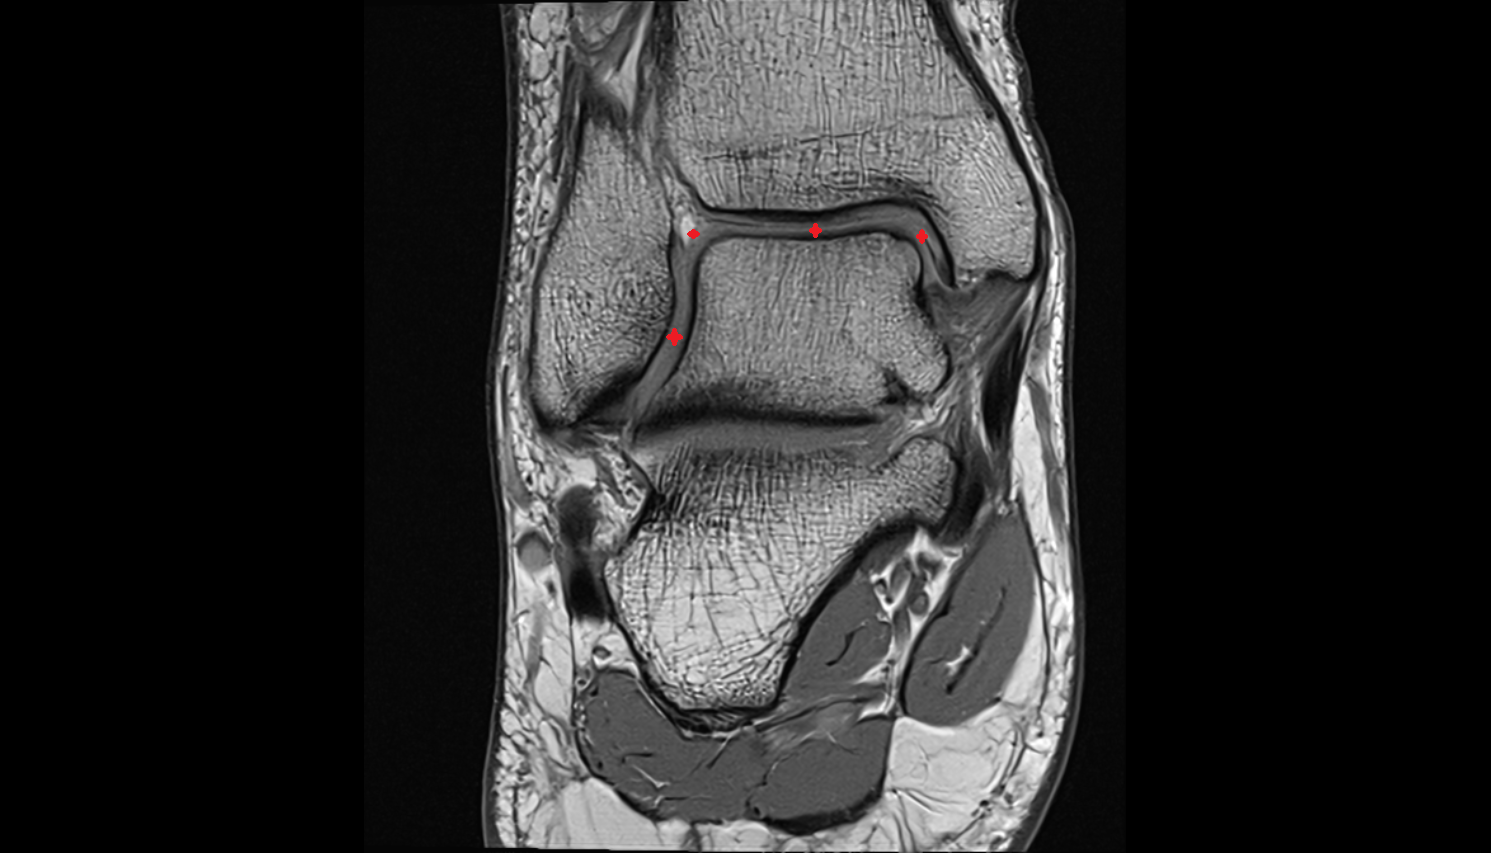

- Meniscus cartilage

- Medial meniscus

- Lateral meniscus

- Anterior horn of medial meniscus

- Posterior horn of medial meniscus

- Body of medial meniscus

- Anterior root of medial meniscus

- Posterior root of medial meniscus

- Anterior horn of lateral meniscus

- Posterior horn of lateral meniscus

- Body of lateral meniscus

- Anterior root of lateral meniscus

- Posterior root of lateral meniscus

- Knee Joint